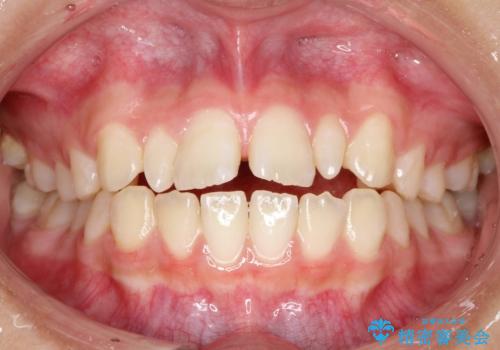

上あごの2番目の歯は矮小歯といって、生まれつき小さい歯となる事がよくあります。

このような場合、矯正によりスペースを集め、本来あるべき形態にセラミックで修正することもできます。

時間はかかりましたが、きれいな笑顔になりました。